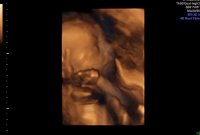

Og jeg er evig takknemlig for at alt ser helt perfekt ut på UL i dag med skikkelig anatomisk gjennomgang, fra hodet til tær, og alt som var fryktelig galt er helt perfekt nå. Er 12+2 i dag, men jordmor målte meg til 12+4, så termin rundt 28 april. Spent på om sykehuset finner det samme på ultralyd neste onsdag. Enn hvor glad jeg er for at jeg har en frisk lillebror i magen, så er jeg ett lite snev skuffet. Skuffet over at jeg ikke får min lille prinsesse Maja, som jeg alltid har drømt om. Vet at jeg blir like glad i lillebror som jeg er i storebror og gutt kan jeg jo, men jeg drømte liksom om å få en jente. Men min jente var syk…

21+4 og tiden går både fort og sent på samme tid…